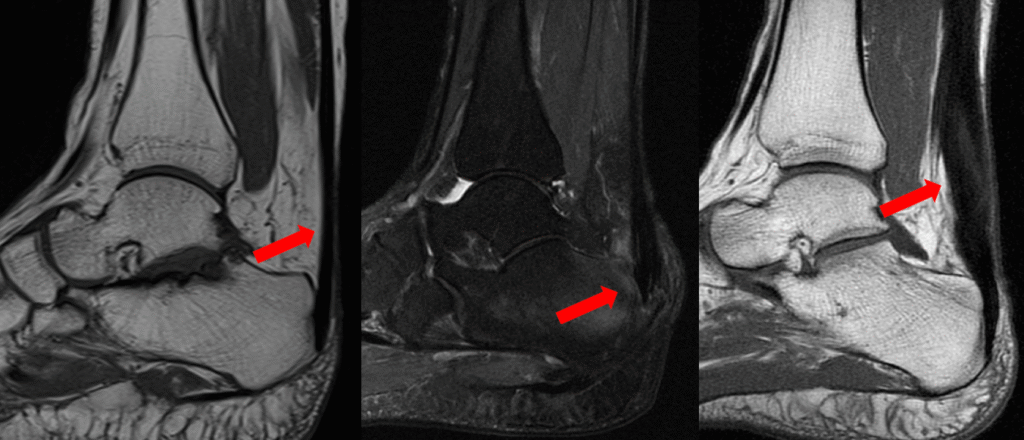

- Aa tendinopatia insercional, aquela que acontece na região onde o tendão se insere no osso e a não insercional, que está relacionada a inflamação e degeneração no corpo do tendão, como mostram as imagens de ressonância magnética na figura abaixo. A tendinopatia insercional tende a ocorrer em pessoas mais ativas

Figura 1: Imagem de ressonância demonstrando da esquerda para a diretia: imagem com tendão normal, imagem com tendinopatia insercional e imagem com tendinopatia no corpo do tendão de aquiles.